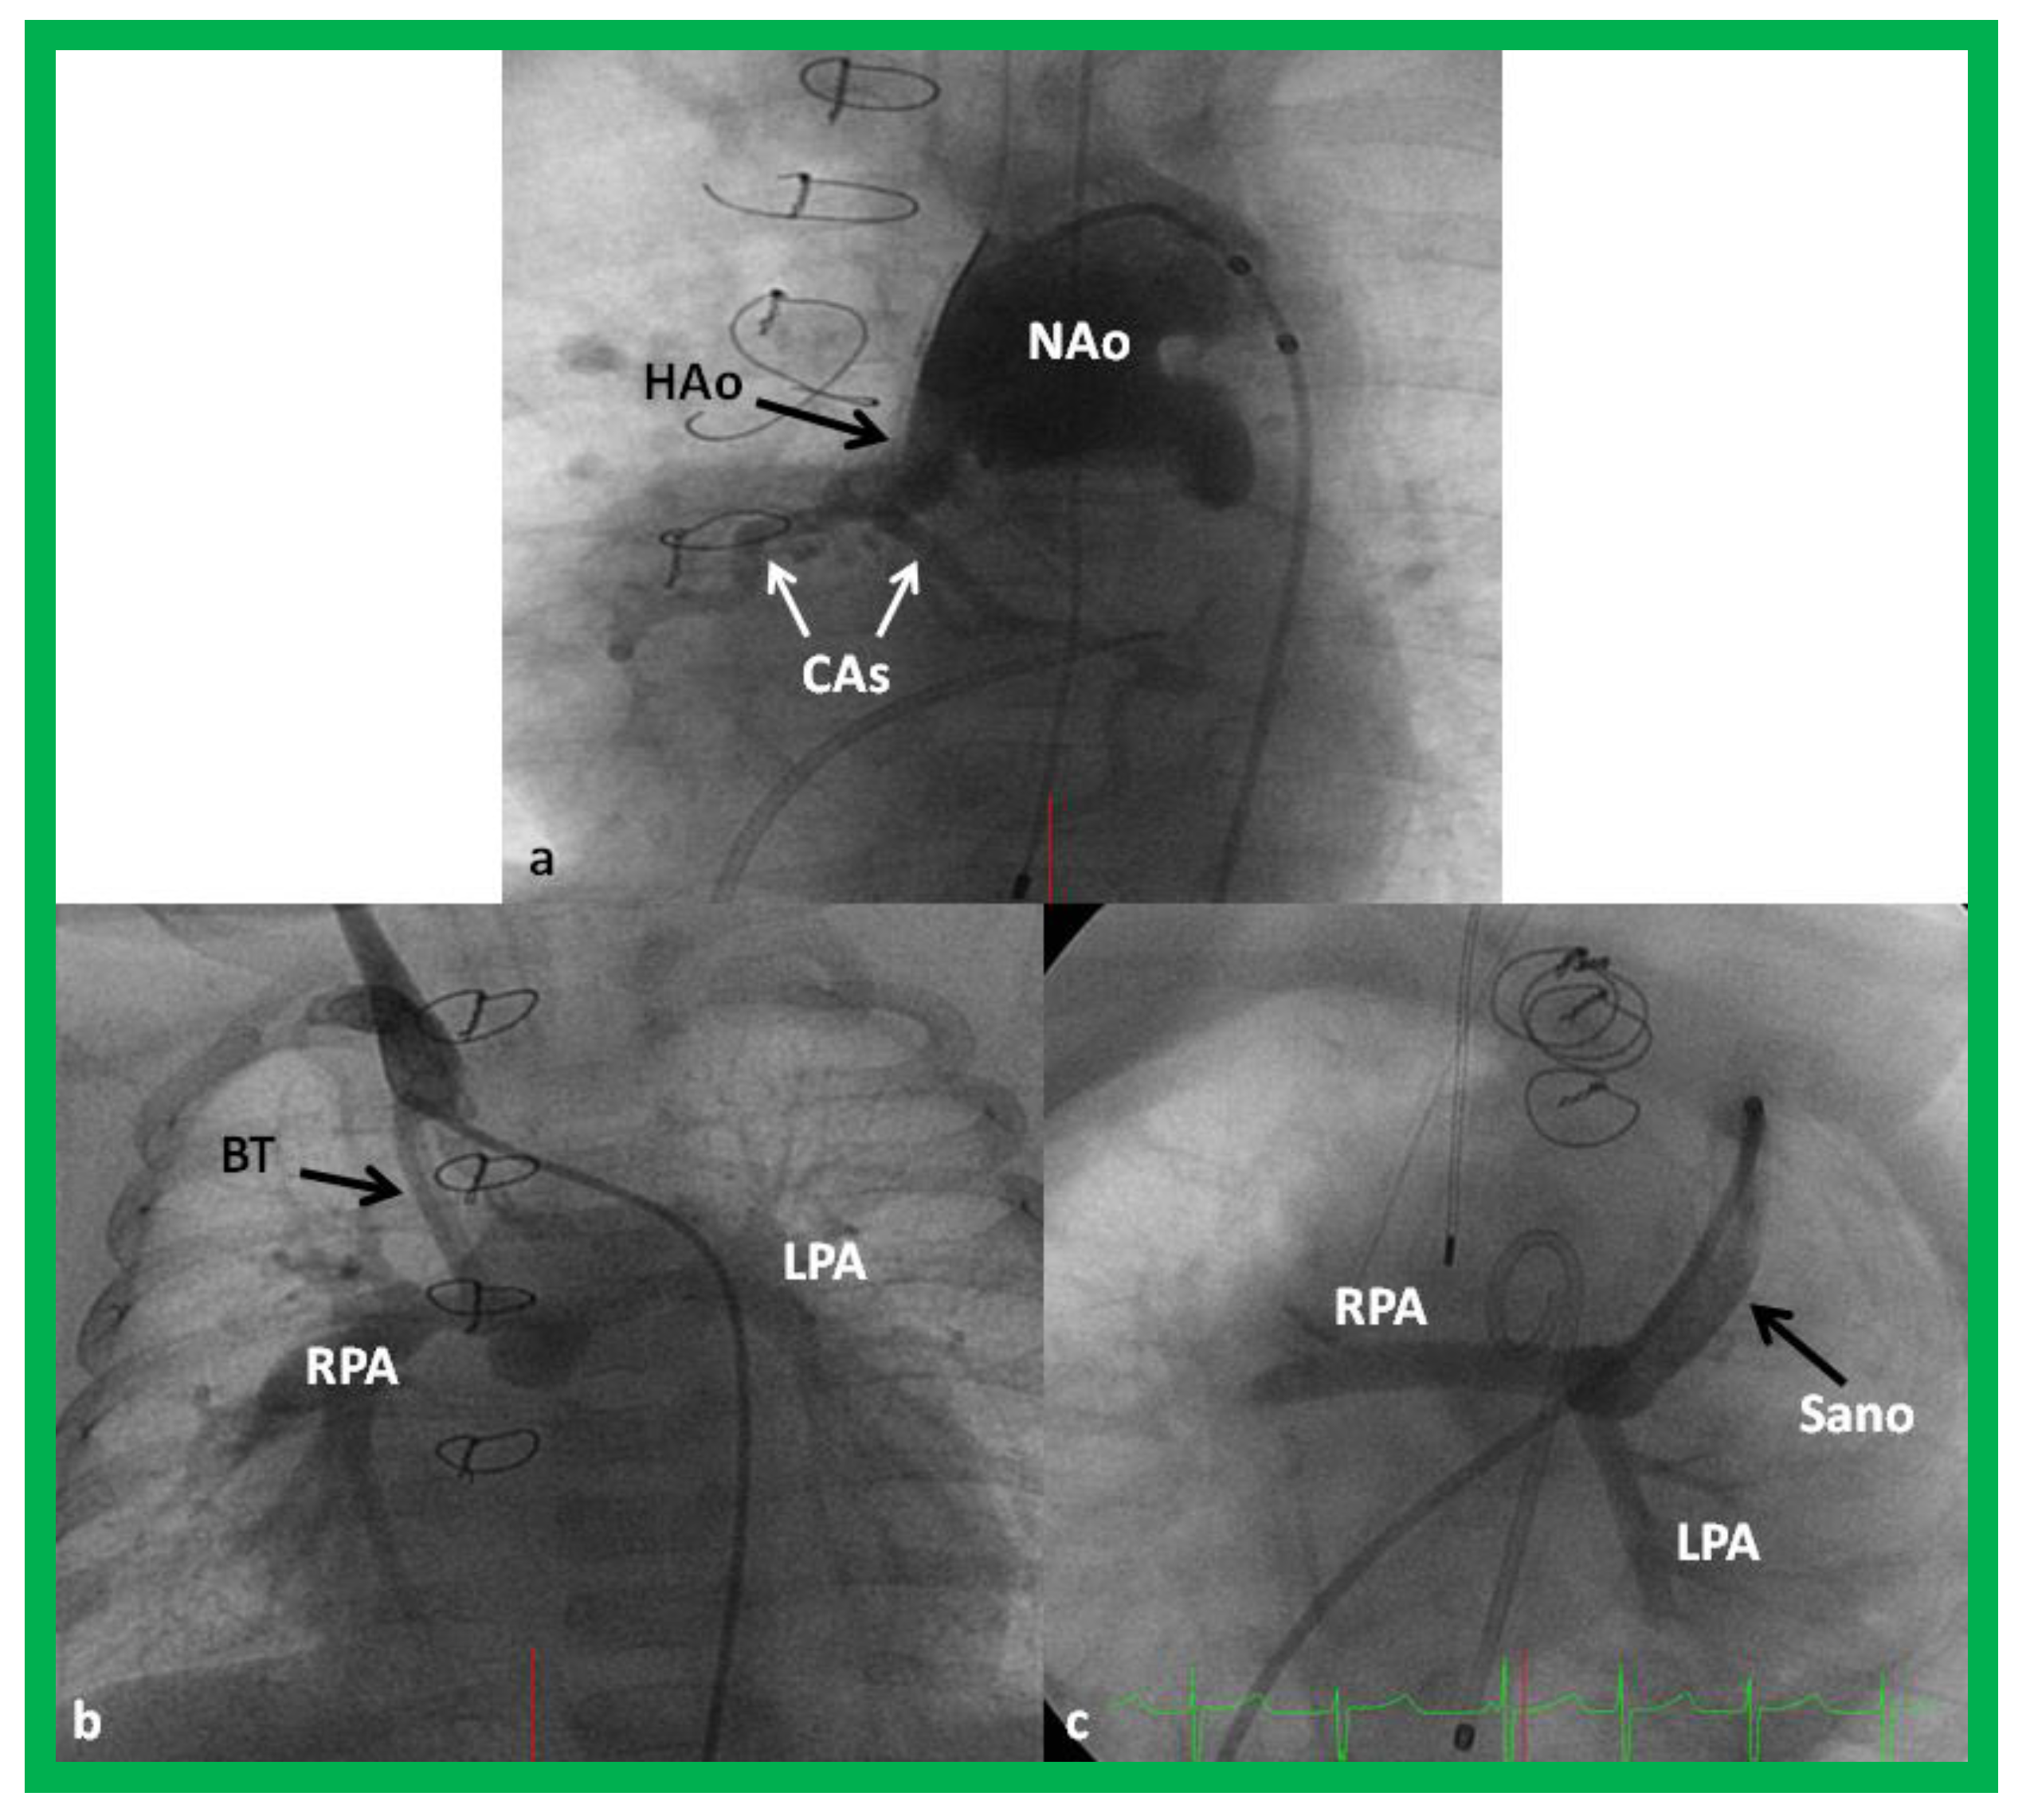

The majority of these babies belong to HLHS syndrome or its variants and require Norwood operation [19,20] with either Modified BT [39] or Sano [48,49] shunt (Figure 11). In some institutions, cardiac transplantation [50] is employed to address this lesion.

Figure 11.

Cineangiogrames demonstrating the Norwood procedure, showing the neoaorta (NAo) and hypoplastic old aorta (HAo). The latter supplies the coronary arteries (CAs) as shown in (a). A Blalock-Taussig (BT) shunt in seen in (b) and a Sano shunt in (c) from two other babies are also shown. This is Stage I of the Fontan procedure for infants with hypoplastic left heart syndrome. LPA, left pulmonary artery; RPA, right pulmonary artery. Reproduced from Reference [33].